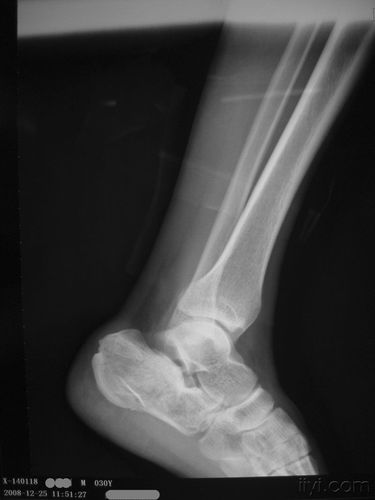

儿童踝关节正常x片